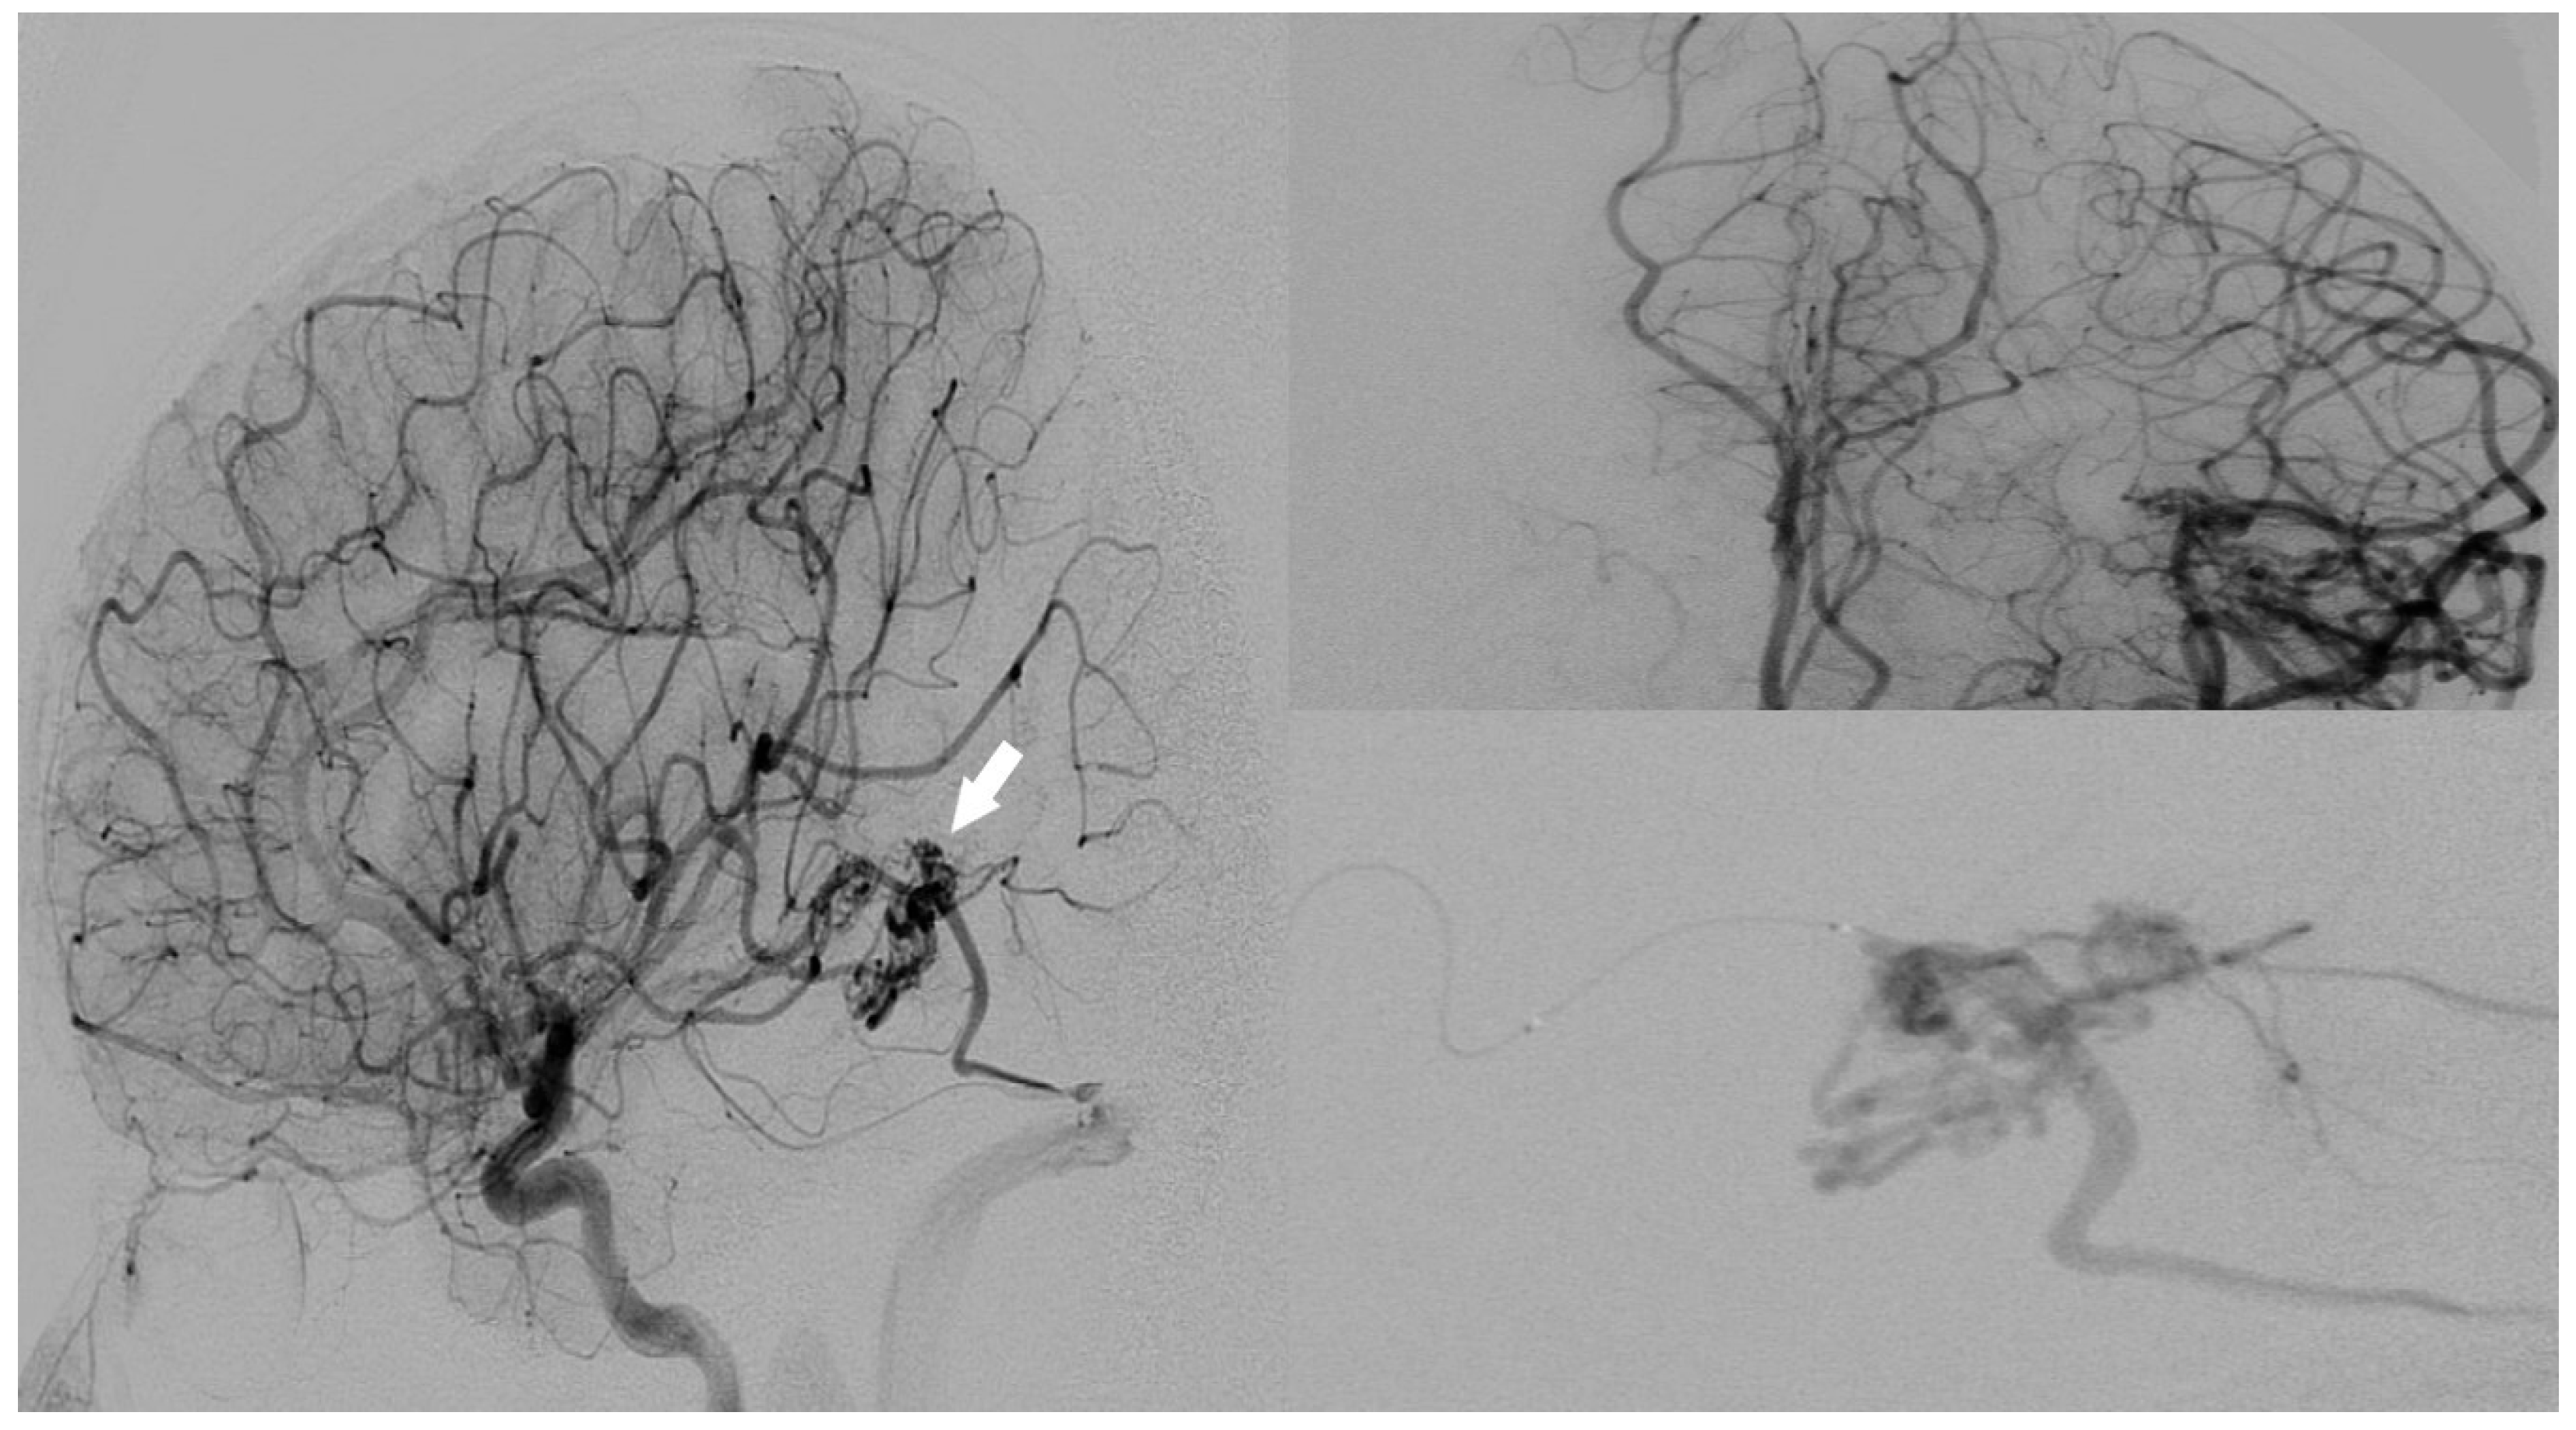

Digital subtraction angiography performed two months later demonstrated a grade 3 [Spetzler Martin Grading Scale] arteriovenous malformation located in the left posterior temporal lobe. The lesion exhibited both superficial and deep venous drainage originating from the posterior temporal branches of the left middle cerebral artery and the left anterior choroidal artery (Figure 6).

A significant stenosis was noted in one of the two draining veins. Additionally, aneurysmal dilatations were observed within the nidus of the malformation. The patient underwent successful endovascular treatment for AVM closure and experienced no neurologic deficits post-procedure. He was discharged without any further complications.

Figure 6. Intracranial arteriovenous malformation visualized on DSA (white arrow marks the nidus).